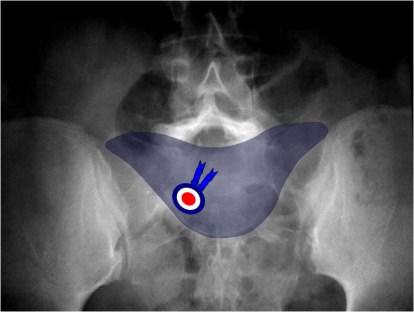

SIGNO DEL SOMBRERO DE NAPOLEÓN INVERTIDO

Signo de espondilolistesis L5-S1 en la radiografía anteroposterior de columna lumbar. El cuerpo vertebral de L5 desplazado y superpuesto al sacro da esta característica apariencia.

Este signo también lo hemos encontrado descrito como Signo de la línea de arco de Brailsford.

La misma imagen anterior con la imagen superpuesta del sombrero de Napoleón boca abajo.